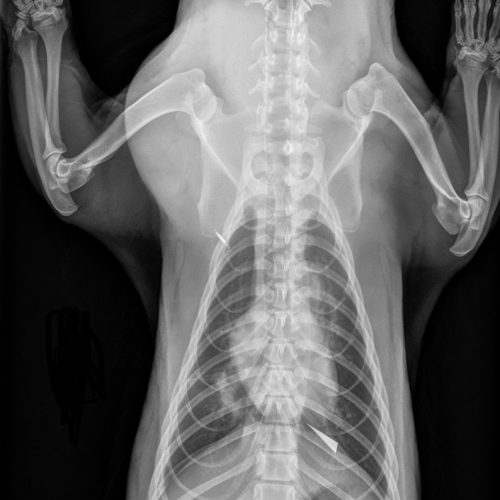

After arriving at Hogle Zoo, our on-site veterinary team conducted a health exam and discovered abnormalities in the badger’s chest and lungs. X-rays revealed a sharp, metallic object in his chest and an object impacting his lung. We then brought him to MedVet for a CT scan to further identify the foreign material and develop a treatment plan.

While Tony was fortunate these items didn’t impact his heart or major blood vessels or rupture a lung, the teams at Hogle Zoo and MedVet determined that surgery was necessary. In November 2023, surrounded by a team of veterinarians and technicians, Board-certified Veterinary Surgeon Dr. Sylvia Lee performed a thoracotomy (an incision between the ribs) at MedVet to remove the objects inside of Tony. Once removed, the objects appeared to be a piece of rusty, sharp metal and a piece of wood.